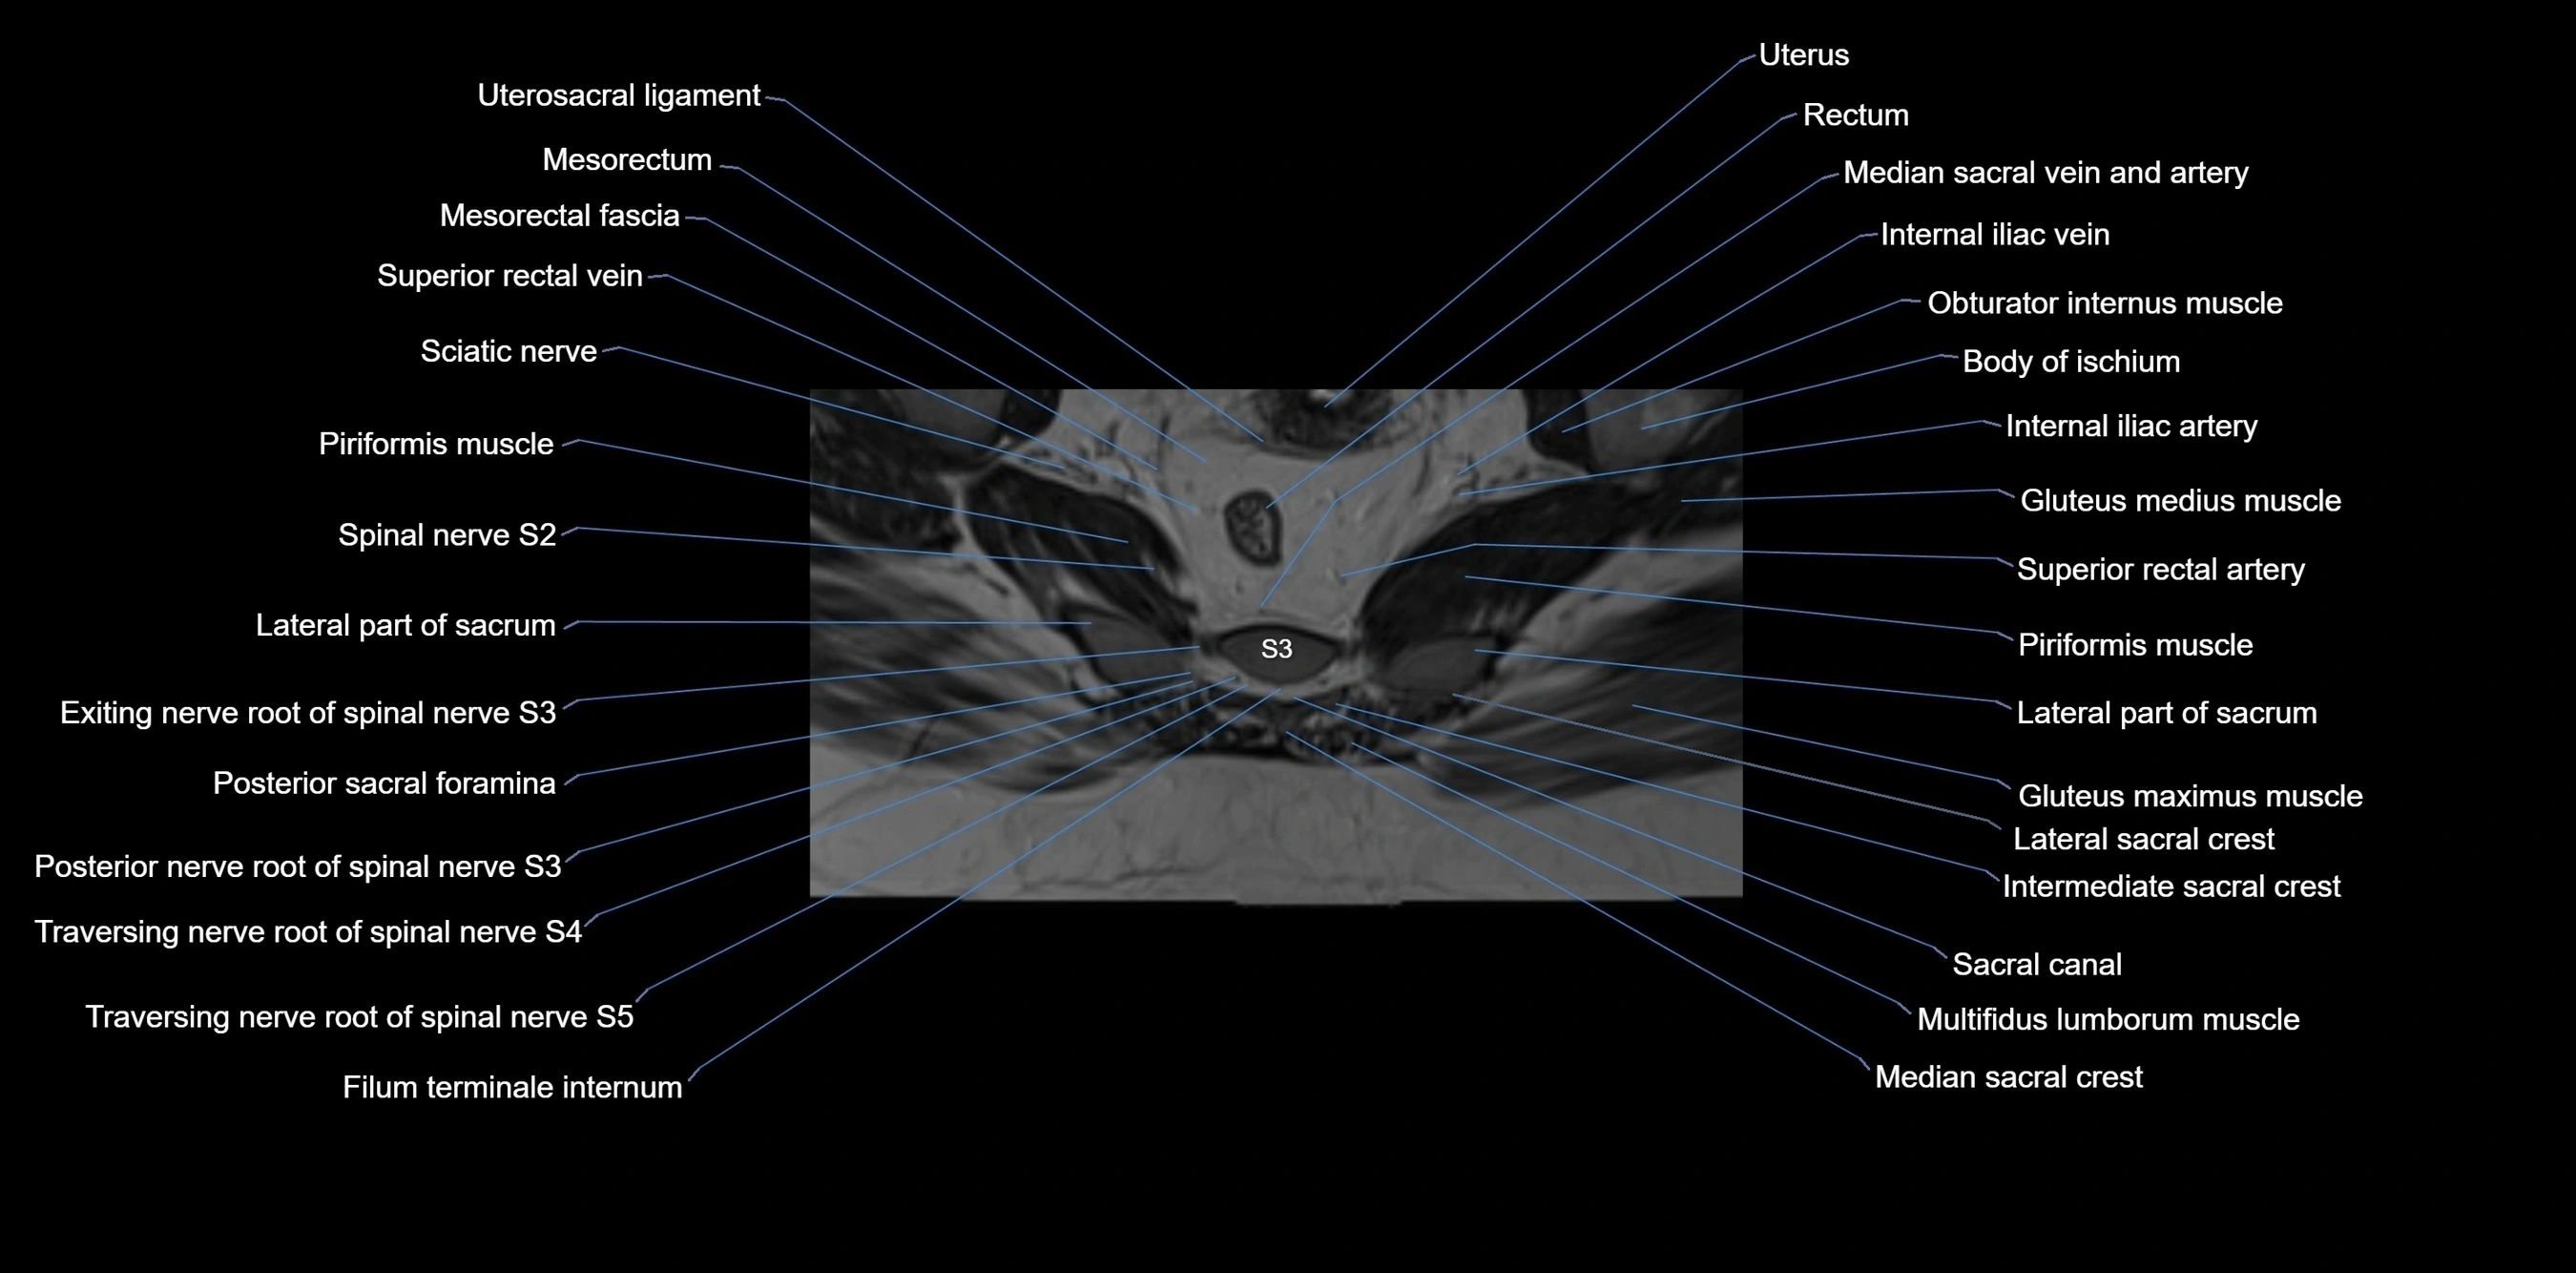

MRI Appearance

T1-weighted images:

• Cortical bone appears very low signal (dark); marrow shows intermediate signal

• Iliac fossa fat is bright against low-signal cortex

T2-weighted images:

• Cortical bone remains dark

• Marrow signal varies depending on fat content; edema or tumor shows hyperintensity

STIR:

• Suppresses fat, making bone marrow edema, fractures, or infiltrative lesions appear bright

• Excellent for trauma, sacroiliitis, and metastatic evaluation

T1 Fat-Saturated (Pre-contrast):

• Marrow: intermediate signal, fat suppressed

• Useful for detecting subtle marrow abnormalities adjacent to iliac cortex

T1 Fat-Saturated Post-Contrast (Gadolinium):

• Enhances vascularized structures, marrow pathology, tumors, and inflammatory changes

• Highlights soft tissue or bone invasion in pelvic neoplasms

MRI Non-Contrast 3D Imaging:

• Provides 3D morphology of iliac wing, crest, and articulations

• Used in preoperative planning for pelvic surgery and trauma reconstruction

MRI image

image